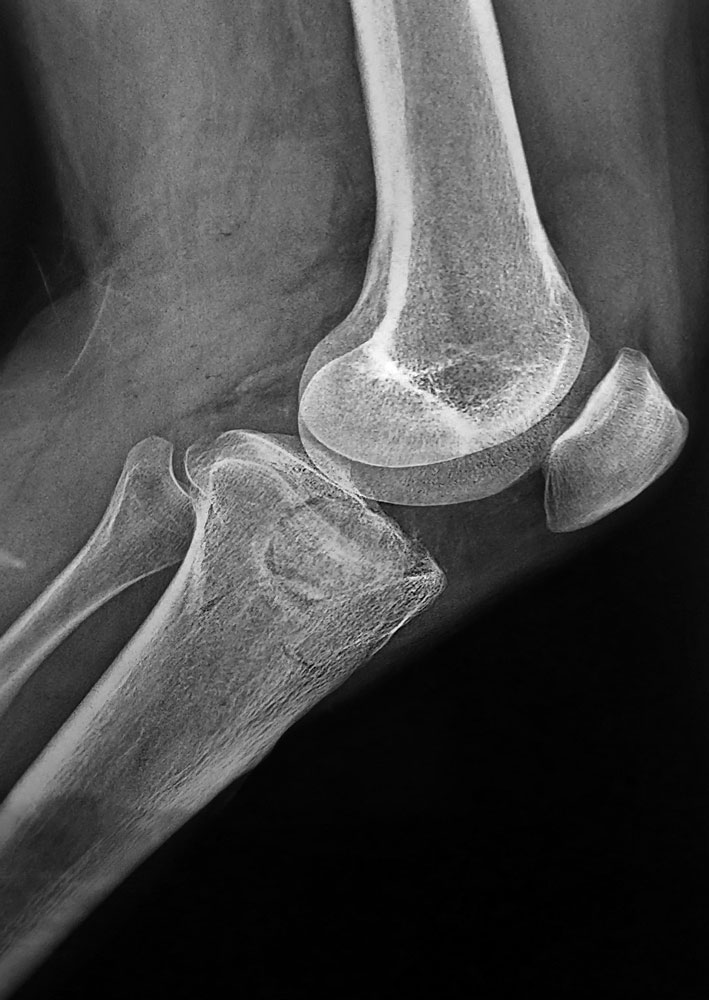

Всем доброго времени суток! Мужчина, 36 лет, импрессионный перелом медиального (внутреннего) мыщелка ББК левой ноги. С его слов обстоятельства травмы: Прыгнул с высоты около 3м и при приземлении подвернул ногу.

Прилагаю снимки ренген + КТПодскажите пожалуйста, какой фиксатор подойдет для данного перелома.

Переломы тибиал плато по Schatzker IV характерны импрессией суставной поверхности без вовлечения медиального кортекса. Из исследований стандартные снимки и КТ. Снимки на вытяжении рекомендуются только при переломах с вовлечением двух мыщелков, а при переломе одного из мыщелков отсутствует укорочение и вытяжение не требуется.

В оперативном лечении это-восстановление суставной поверхности из медиального окошка и удержание от варусного коллапса. Приподнять суставную поверхность до уровня, дефект кости заполнить аутокостью или синтетическими заменителями, затем закрыть "форточку". Из-за отсутствия медиальных специальных пластин можно применить пластины: более мощная-Distal humerus extra articular plate (Synthes) когда вовлекается большие фрагменты или VLP Smith Nephew, которая легко формируется под кость.

Но данный вариант перелома позволяет обойтись более легкой конструкцией (method Raft)-параллельными винтами, 3.5 мм кортикальные и ближе к суставу. Чем больше винтов, тем лучше создается опорная крыша, а более стабильная конструкция создается дополнением 1/3 трубчатой пластиной, которую можно пустить вокруг переднего края тибиа. Винты через пластину или винтами отдельно с шайбой.